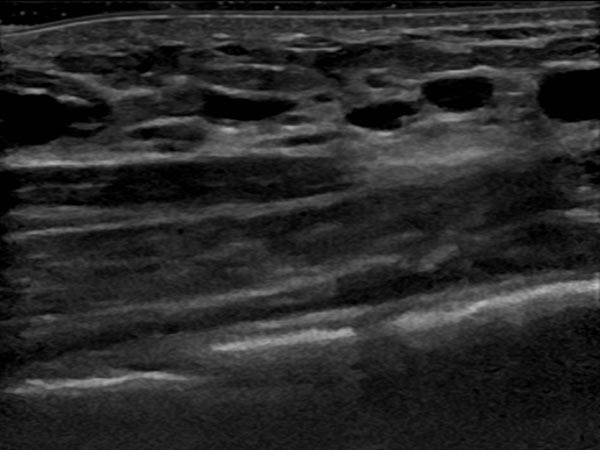

In der Ultraschallkontrolle 6 Monate nach der 2. Therapie sind nur noch sehr kleine zystische Anteile der LM nachzuweisen. Die größeren Zysten sind verschlossen. Da die Patientin asymptomatisch ist können diese bei einer an sich benignen Läsion belassen werden.

Die Schwellung der Bauchwand durch die LM ist praktisch vollständig zurückgebildet. Die Patientin hat keine Schmerzen mehr. Das Lymphangioma circumscriptum ist abgedichtet und hat sich zurückgebildet.